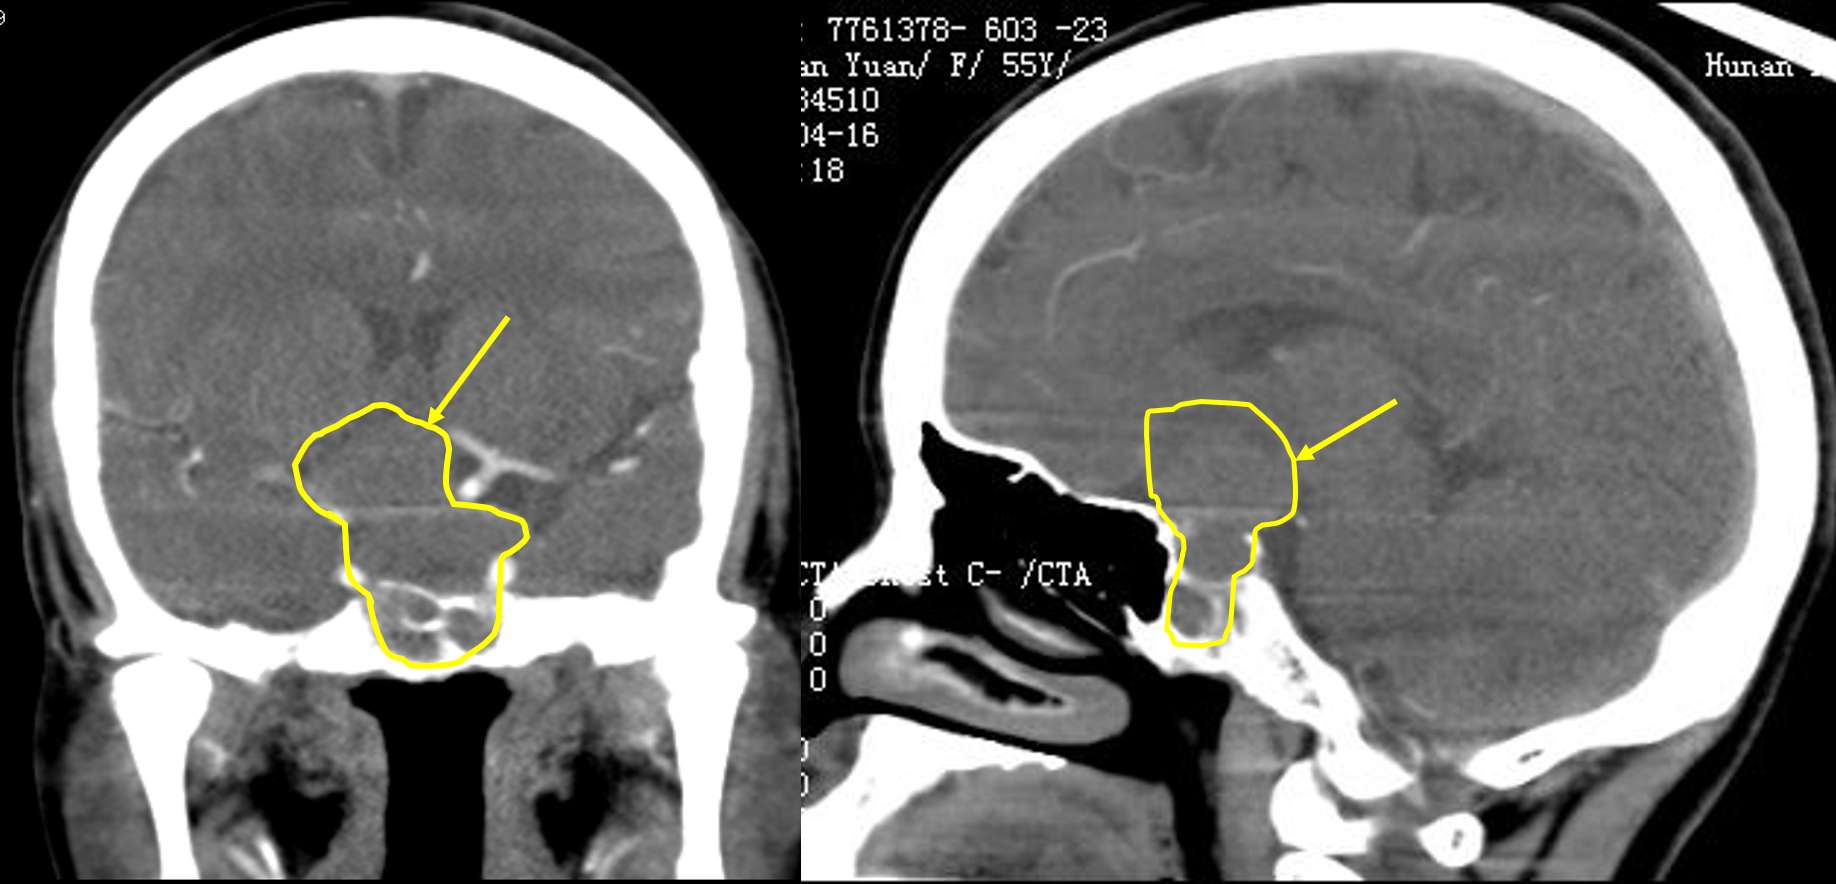

患者入院后经过详细检查,肿瘤为无功能性肿瘤,不分泌内分泌激素,影像学提示垂体肿瘤往鞍上生长,并紧邻颈内动脉,属于巨大垂体瘤,手术风险很大。

经过科室讨论和院内多学科会诊,并与患者及家属充分沟通后,患者家属决定选择在鼻内镜下微创行经鼻垂体瘤切除术,我们在术中采取双人三手、双人四手操作,密切配合,完整切除肿瘤,并保护了鞍膈的完整性,双侧颈内动脉也未受损,术中出血约350ml,未出现脑脊液漏,未输血。术后鼻腔填塞少量止血材料,患者无明显头痛等不适,术后第一天,左眼视力即由原来的只能感觉眼前的手动,升为可以辨别眼前的手指个数了,提示明显改善。术后尿量在正常范围,未出现尿崩(垂体瘤术后常见的并发症之一)。术后复查CT提示,垂体肿瘤切除干净。患者术后一周即出院了。